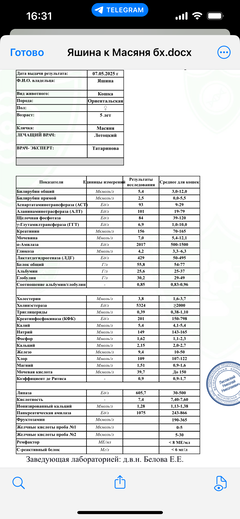

Была куплена в питомнике взрослой. У Масяни начались проблемы с кишечником и она стала подтекать и все пачкать. Надо отдать должное хозяевам - ее обследовали вдоль и поперек - как говорили местные врачи, сдавали много анализов но диагноза так и не поставили.

Ярко выраженная болезненность в области крестца, на обезболе полегче. По результатам приема невролога проведена миелография - множественная компрессия, возможно опухоль, возможно грыжа, нужно удалять...